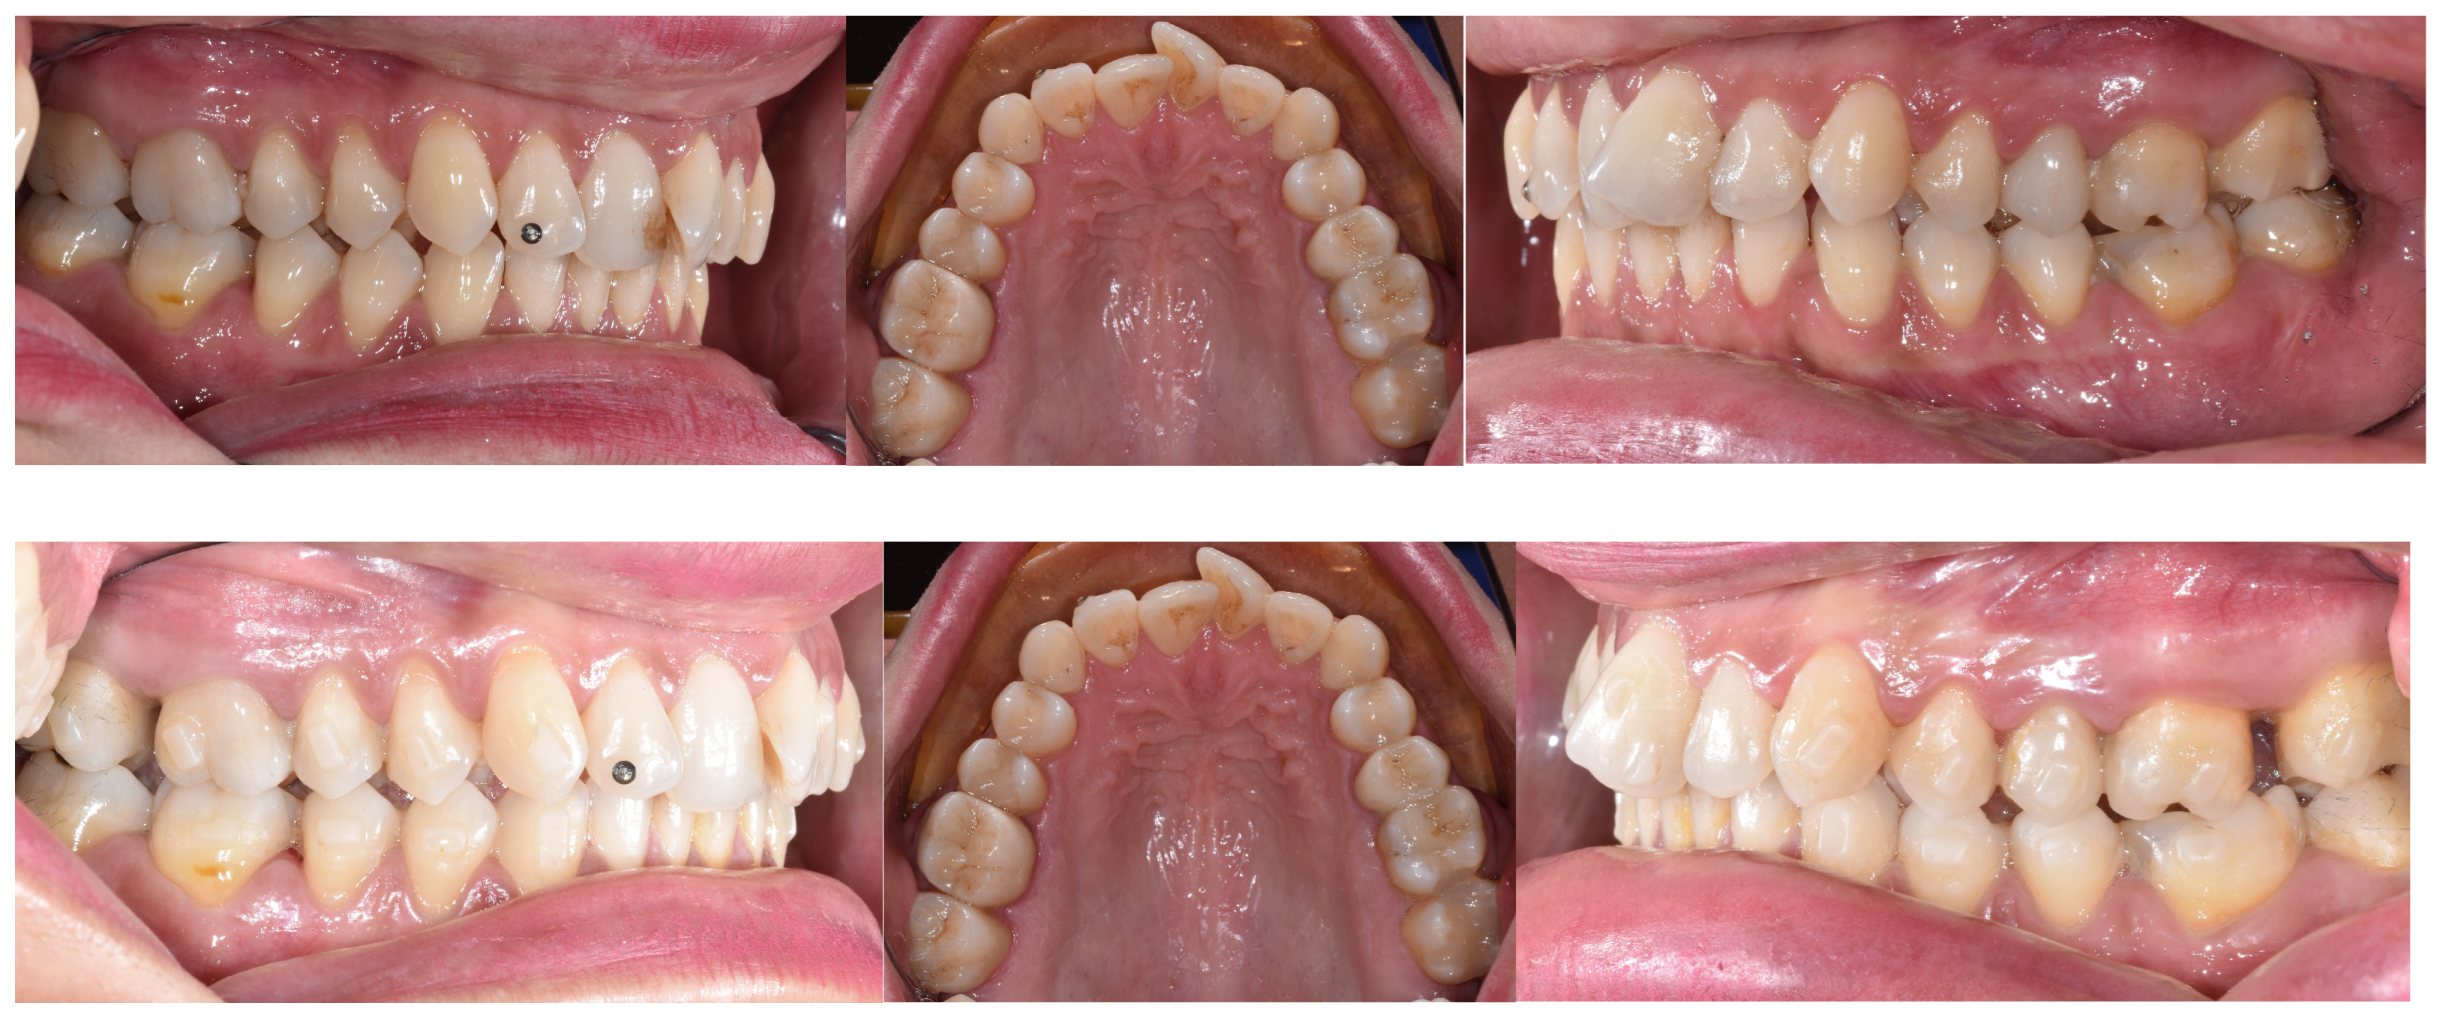

- Staderini, E.; Ventura, V.; Meuli, S.; Maltagliati, L.Á.; Gallenzi, P. Analysis of the Changes in Occlusal Plane Inclination in a Class II Deep Bite “Teen” Patient Treated with Clear Aligners: A Case Report. Int. J. Environ. Res. Public Health 2022, 19, 651. [Google Scholar] [CrossRef] [PubMed]

- Pinho, T.; Rocha, D.; Ribeiro, S.; Monteiro, F.; Pascoal, S.; Azevedo, R. Interceptive Treatment with Invisalign® First in Moderate and Severe Cases: A Case Series. Children 2022, 9, 1176. [Google Scholar] [CrossRef] [PubMed]